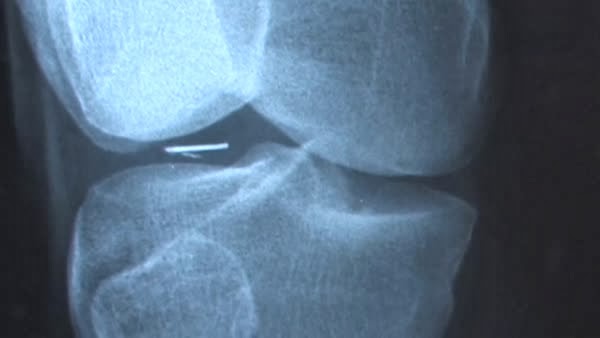

История началась летом 1995 года, когда Лир получил заказное письмо от Дэррила Симса с просьбой дать медицинское заключение по рентгеновскому снимку. Это стало отправной точкой для серии операций и исследований, в ходе которых были извлечены крошечные предметы неизвестного происхождения.

Один из случаев описывается так: пациент, названный Пэтом Паринелло, вспомнил эпизод из детства, когда в шесть лет он внезапно вышел на улицу и увидел яркий свет над городом, затем почувствовал сильную боль, как от горячей иглы в руке, и проснулся наутро с температурой и кровью на простыне. Позже у него из пальца извлекли посторонний предмет.